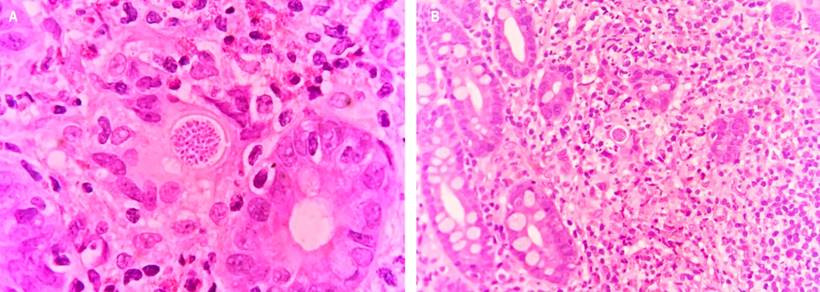

En el estudio anatomopatológico de la biopsia endoscópica de la lesión se identificó una duodenitis aguda y crónica ulcerada con un componente granulomatoso y abundantes blastoconidias compatibles con Coccidioides spp (Figura 2).

Figura 2 Esférulas con endosporas en una biopsia de mucosa duodenal con infiltrado inflamatorio mixto con neutrófilos, histiocitos epitelioides y eosinófilos. Fuente: Departamento de Patología, Hospital Universitario del Valle.